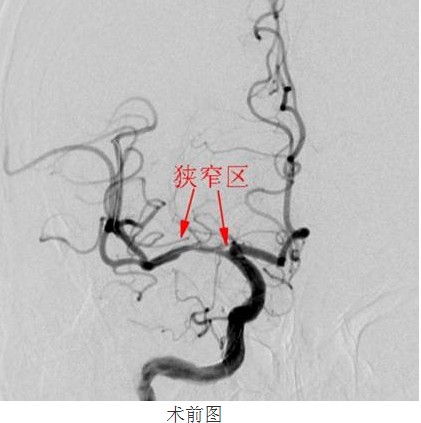

经过数天的积极治疗,患者行头颅MRI+MRA检查,结果和颜医生判断一致:右侧基底节区额、顶、颞、枕叶白质区脑梗塞,脑动脉硬化,右侧大脑中动脉M1段不规则重度狭窄,分支血管减少。为了进一步明确右侧大脑中动脉狭窄的程度及其他脑血管代偿能力,是否达到神经介入治疗的指征,21颜津津主治医师医生为患者进行了DSA脑血管造影(判断血管狭窄的金标准)进一步证实磁共振检查提示,右侧大脑中动脉M1近端狭窄,程度约80%,长度约12cm

常规准备后,神经内科颜津津主治医师在助手高彬医师配合下采用Seldinger法穿刺股动脉,置导管鞘、引导管,在导丝带引下将导引导管放置右侧颈内动脉岩部造影,后在透视下,顺着造影路图,小心将微导丝、微导管通过狭窄处并置入右侧大脑中动脉M3段,接着撤出微导管,顺着微导丝置入Gateway球囊, 至狭窄部位,经造影骨性标志等多重定位后证实球囊位置良好,接压力泵缓慢加压扩张,撤出球囊造影,显示血管成形良好。选取Wingspan支架, 顺微导丝将支架输送器小心送至狭窄处,造影定位确认支架位置准确覆盖狭窄部位,释放支架,撤出支架输送器,造影证实血管狭窄处成形良好,观察10分钟后再次造影,支架无移位,狭窄处远端血管完整,未见血管狭窄、造影剂外渗。撤除导丝、导引导管,患者术后24小时可下床自行活动,术后1周顺利出院,生活基本恢复正常,并叮嘱梁伯继续坚持服药,定期复诊。